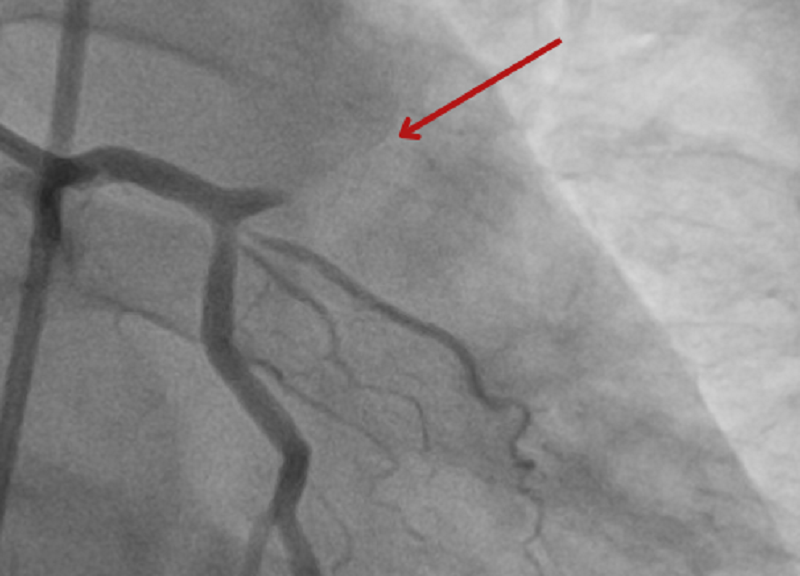

| Hình ảnh kiểm tra cho thấy bệnh nhân bị tắc gần như hoàn toàn động mạch vành bên trái |

Kết quả chụp mạch vành cho thấy bệnh nhân bị tắc hoàn toàn đoạn gần của động mạch vành trái. Các bác sĩ đã quyết định thực hiện phương pháp can thiệp nội mạch để nong mạch vành và đặt stent tại vị trí mạch máu bị tắc.